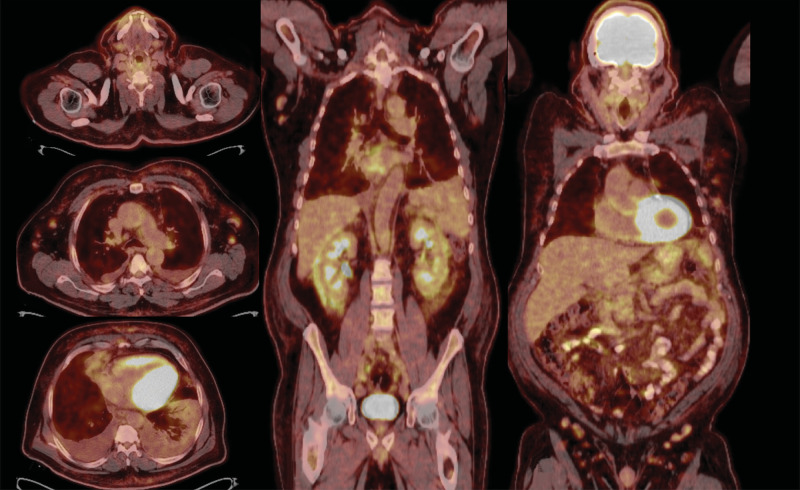

Mycosis fungoides is the most commonly seen type of cutaneous T-cell lymphoproliferative disease. While mycosis fungoides is linked to an increased risk of developing secondary malignancies, the occurrence of B-cell-originated disease in association with it is exceedingly rare. A 66-year-old male with persistent papillomatous skin eruption was admitted due to dyspnea. Chest X-ray, positron emission tomography, and chest computed tomography revealed axillary and mediastinal lymph node enlargement and right lower pulmonary lobe infiltration along with right-sided massive pleural effusion. Histological and immunohistochemical findings of pleural biopsy and axillary lymph nodes suggested a diagnosis of pulmonary extranodal marginal zone lymphoma. Skin biopsies from the abdomen, chest, and legs revealed CD4/CD8 double-positive patch stage of mycosis fungoides. After completing six cycles of chemotherapy, complete remission of lymphoma was achieved, with the skin eruptions remaining unchanged. Herein, the authors present a unique case of concomitant diagnoses of mycosis fungoides and marginal zone B-cell lymphoma of the respiratory system to emphasize the importance of careful evaluation of each finding.